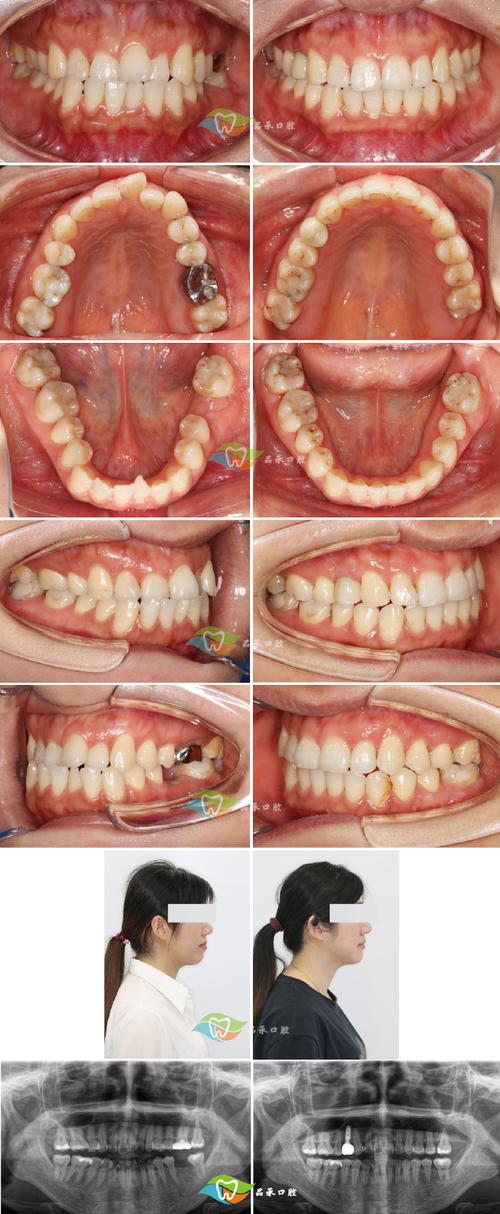

下颌骨前突畸形主要表现为下颌角过大、下巴前伸、侧面观呈“月牙脸”,严重者可能伴随上颌骨发育不足、牙齿反颌(下前牙覆盖上前牙)、咀嚼效率低下、发音不清,甚至颞下颌关节紊乱,手术的核心目标包括:矫正下颌骨前突或旋转异常、建立正常的咬合关系、改善面部侧貌对称性、恢复口腔功能。

- 影像学检查:拍摄头颅侧位片、曲面断层片、CT三维重建,测量下颌骨长度、角度、牙根位置,模拟手术截骨量和移动方向;